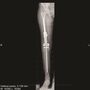

O tom, že my Češi máme obrovskou invenci, nás mohou přesvědčit významné originální české produkty. V tomto případě z oblasti, která kombinuje medicínu a moderní technologie. V tomto díle našeho seriálu vám představíme revoluční miniinvazní rostoucí endoprotézu stehenní kosti, která může zajistit kvalitní budoucí život dětským pacientům s kostním tumorem.